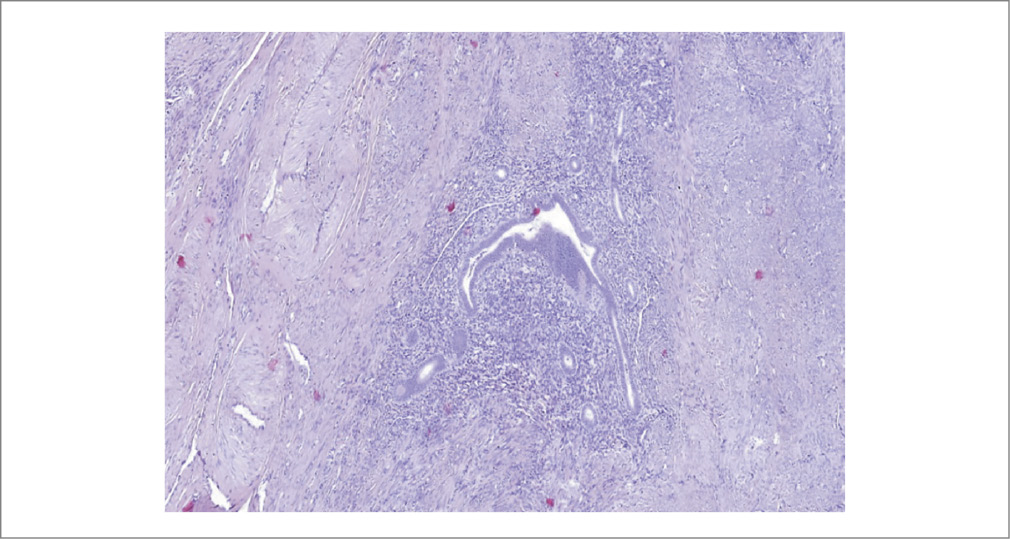

Результат патоморфологического исследования биопсийного материала (серо-розовая ткань плотно-эластичной консистенции, на разрезе белесоватого цвета, слоистого вида) представлен фрагментами новообразованной ткани, хаотично располагающимися мышечными волокнами с неравномерным разрастанием соединительной ткани, с фокусами соединительной ткани с участками, представленными эндометриоидными железами и стромой, по периферии – макрофаги, фагоцитирующие гемосидерин (рис. 3). При иммуногистохимическом исследовании выявлена умеренно выраженная экспрессия рецепторов эстрогена и прогестерона в клетках и железах эндометрия (рис. 4–8).

Рис. 3. Резецированная ткань аденомиомы. Видны полости, которые заполнены геморрагическим содержимым.

Fig. 3. Resected adenomyoma tissue. Cavities filled with hemorrhagic contents are visible.

Аденомиотические кисты типично для аденомиоза выстланы эутопической функциональной тканью, подобной базальному слою эндометрия, и характеризуются циклическими изменениями с десквамацией эпителия и геморрагическим инфарктом прилегающих гладких мышц [10–12]. Согласно исследованию P. Acien и соавт. [13] критерии морфологической диагностики кистозного аденомиоза – патологическая полостная структура в миометрии, выстланная эндометриальным эпителием с железами и стромой, часто шоколадно-коричневое жидкое содержимое.